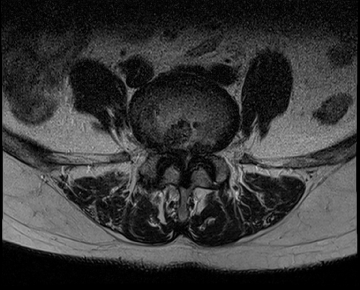

요추 협착증 수술 전·후

2022.08.11

2022.08.16

ㆍ환자 동의를 받은 자료이며, 이미지 사진은 실물과 다를 수 있습니다.

ㆍ모든 자료는 새움병원 자료입니다.